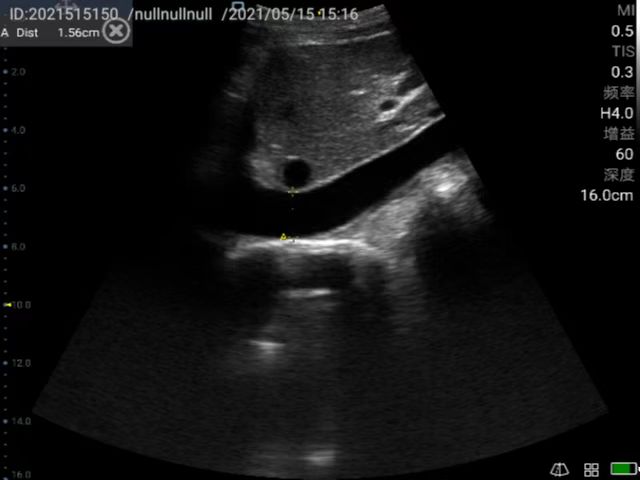

Taking obstetric screening in basic medical care as an example, P50 can accurately screen fetal development anytime, anywhere.

General practice use (mainly divided into ultrasound diagnostic systems for cardiovascular, abdominal, superficial organs, fetus, abdominal large blood vessels and limb blood vessels. Superficial organs mainly include diseases of thyroid, breast, eye, testis, scrotum, etc. Generally, high-frequency probes are used. Abdominal organs are mainly divided into digestive system, urinary system, gynecology, including uterus, accessories and other diseases. Fetal diagnosis in normal fetuses in the early, middle and late stages, mainly observe fetal growth and development, examination of Amniotic fluid, umbilical cord, placenta. Vascular ultrasound diagnosis, including carotid artery, abdominal large blood vessels and blood vessels of limbs, to know whether there is plaque and stenosis in arteries, and whether there is thrombus in veins; for the heart, mainly detect whether there are abnormalities in intracardiac structure and hemodynamic changes.), remote diagnosis.